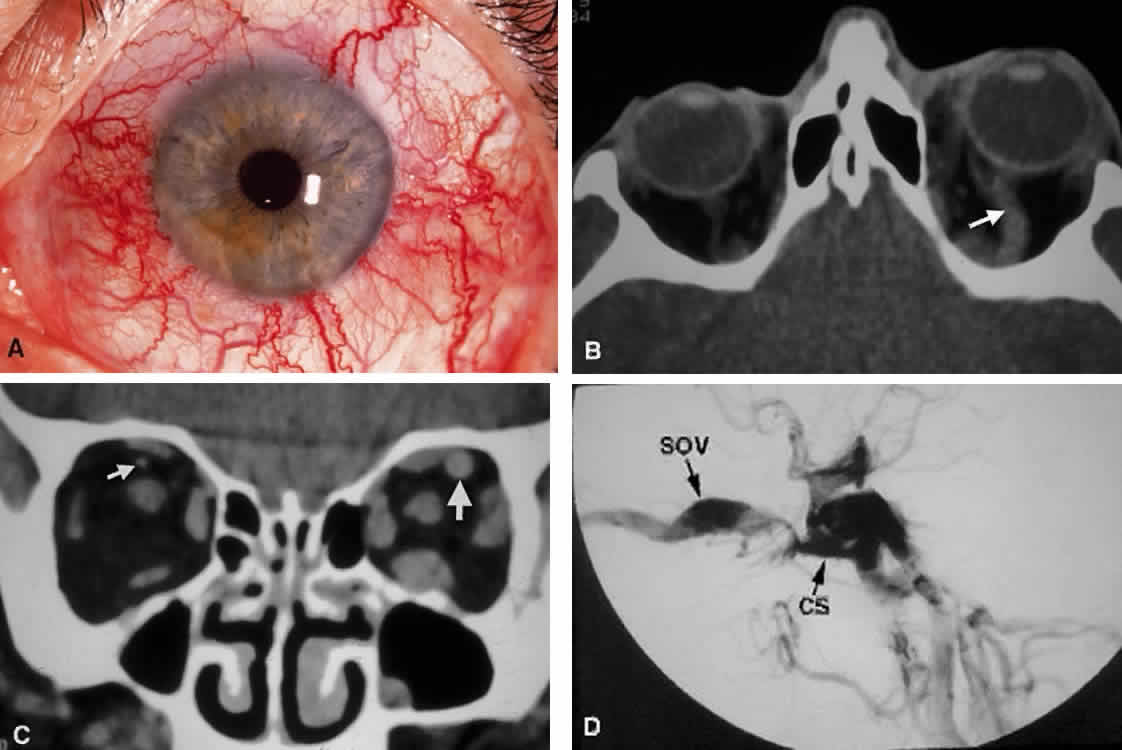

of the CS. An abnormal communication between the arterial and venous supply

of the CS results in either a carotid-cavernous fistula or a dural-sinus

fistula (Fig. 18A). Because of the larger caliber of the ICA, a carotid-cavernous fistula

is usually symptomatic secondary to a high flow state, possibly manifesting

as orbital/ocular ischemia and increased intraocular pressure. This

type of fistula is most commonly encountered in younger patients

after blunt trauma and may require invasive neuroradiologic treatment (Fig. 18B). Conversely, a dural-sinus fistula is typically a low-flow state because

the abnormal communication forms between the small-caliber dural arterial

feeders of the lateral CS wall and the venous plexus of the CS. Such

fistulas are usually seen in older individuals as a spontaneous

event. Depending on the severity of symptoms, most dural sinus fistulas

are simply followed by observation because of the high rate of spontaneous

closure.  Fig. 18. Carotid-cavernous fistula. A. Clinical photograph demonstrating tortuosity of the arteriolized episcleral

veins, extending up to the limbus (the vascular congestion of conjunctivitis

usually ends 1 mm short of the limbus). B. Axial CT shows the difference in caliber between the uninvolved superior

ophthalmic vein and the involved vein (arrows). C. Coronal image likewise shows the difference in venous size (arrows). Also note the enlargement of the extraocular muscle on the involved

side, indicative of orbital congestion. The superior ophthalmic vein is

always found beneath the superior rectus muscle, to which it is tethered

by a hammock-like fascial slip. On the involved side, orbital congestion

and enlargement of the vein cause distortion of this anatomic

relation. D. Parasagittal arteriography image of a different patient shows abnormal

arterial filling of the CS, extending anteriorly into the orbit through

an engorged superior ophthalmic vein (SOV). Fig. 18. Carotid-cavernous fistula. A. Clinical photograph demonstrating tortuosity of the arteriolized episcleral

veins, extending up to the limbus (the vascular congestion of conjunctivitis

usually ends 1 mm short of the limbus). B. Axial CT shows the difference in caliber between the uninvolved superior

ophthalmic vein and the involved vein (arrows). C. Coronal image likewise shows the difference in venous size (arrows). Also note the enlargement of the extraocular muscle on the involved

side, indicative of orbital congestion. The superior ophthalmic vein is

always found beneath the superior rectus muscle, to which it is tethered

by a hammock-like fascial slip. On the involved side, orbital congestion

and enlargement of the vein cause distortion of this anatomic

relation. D. Parasagittal arteriography image of a different patient shows abnormal

arterial filling of the CS, extending anteriorly into the orbit through

an engorged superior ophthalmic vein (SOV).

|